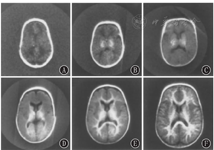

下图列出的是每个脑损伤类别中有代表性的个体婴儿[15](轴位T2加权MRI扫描显示)(图16)。

点击查看大图

图16

每个脑损伤类别中有代表性的个体婴儿轴位T2加权磁共振成像结果 A:足月婴儿(对照);B:极早产的婴儿,无脑损伤,存在折叠减少,解剖结构正常;C:极早产儿,Ⅲ/Ⅳ级IVH,可见脑室内和脑室周围出血;D:极早产儿伴IVH和出血后脑积水,侧脑室扩张;E:极早产儿伴有囊性脑室旁白质软化症

Figure 16

Representative individual infant axial T2 weighted magnetic resonance imaging results in each brain injury category A:full-term infant;B:very preterm infant without brain injury,note dolichocephalic shape and decreased folding but otherwise normal anatomy;C:very preterm infant with grade Ⅲ/Ⅳ IVH,note presence of intra-and periventricular hemorrhage;D:very preterm infant with IVH and post-hemorrhagic hydrocephalus requiring neurosurgical intervention,note dilated lateral ventricles;E:very preterm infant with cystic periventricular leukomalacia